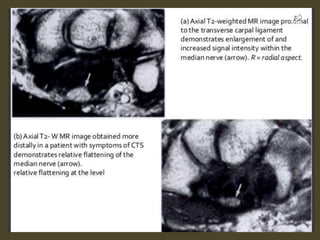

The transverse carpal ligament (short arrows) extends from the hook of the hamate (long

arrow) to the tubercle of the trapezium (arrowhead), forming the floor of the carpal tunnel.

At the radial aspect of the carpal tunnel, the flexor digitorum tendons are arranged in two

rows (separated by dotted line), the profundus tendons deep to the superficialis tendons. The

flexor pollicis longus tendon (star) is positioned at the ulnar aspect of the tunnel, separated

from the flexor carpi radialis tendon (curved arrow) by a ligamentous reflection of the

transverse carpal ligament. The median nerve is indicated (asterisk). - See more at:

http://radsource.us/palmar-bursae-and-flexor-tendon-sheaths/#sthash.mSFX1u0c.dpuf

Swelling, deformity, abnormal signal of the median

nerve.